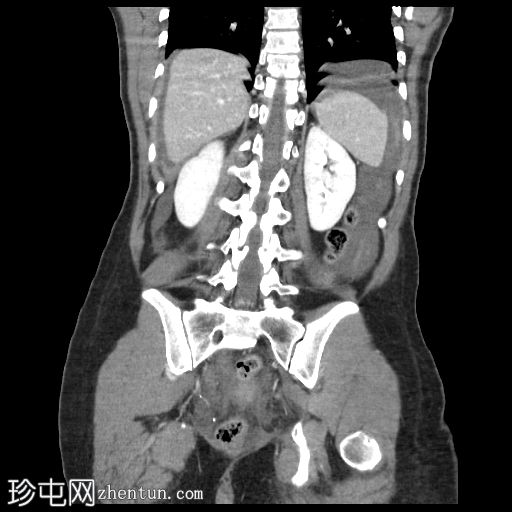

轴位增强扫描

动脉期

子宫增大,复旧不全,子宫体前壁全层缺损,位于近期剖宫产部位,气体和液体从子宫内膜腔经壁缺损扩散至子宫外旁组织。

膀胱瓣膜血肿和腹壁血肿较大。

腹腔内有大量游离液体和血腹,无活动性出血。

剖宫产术后子宫破裂是一种罕见但严重的并发症。 CT扫描显示子宫前壁全层存在不规则的低密度缺损,而子宫前壁其他部分则呈规则强化。

气体或液体通过子宫壁缺损从子宫内膜腔扩散至腹膜腔或宫旁腔,可提高诊断的特异性。

辅助征象包括腹腔积血、盆腔血肿和腹腔内游离液体。